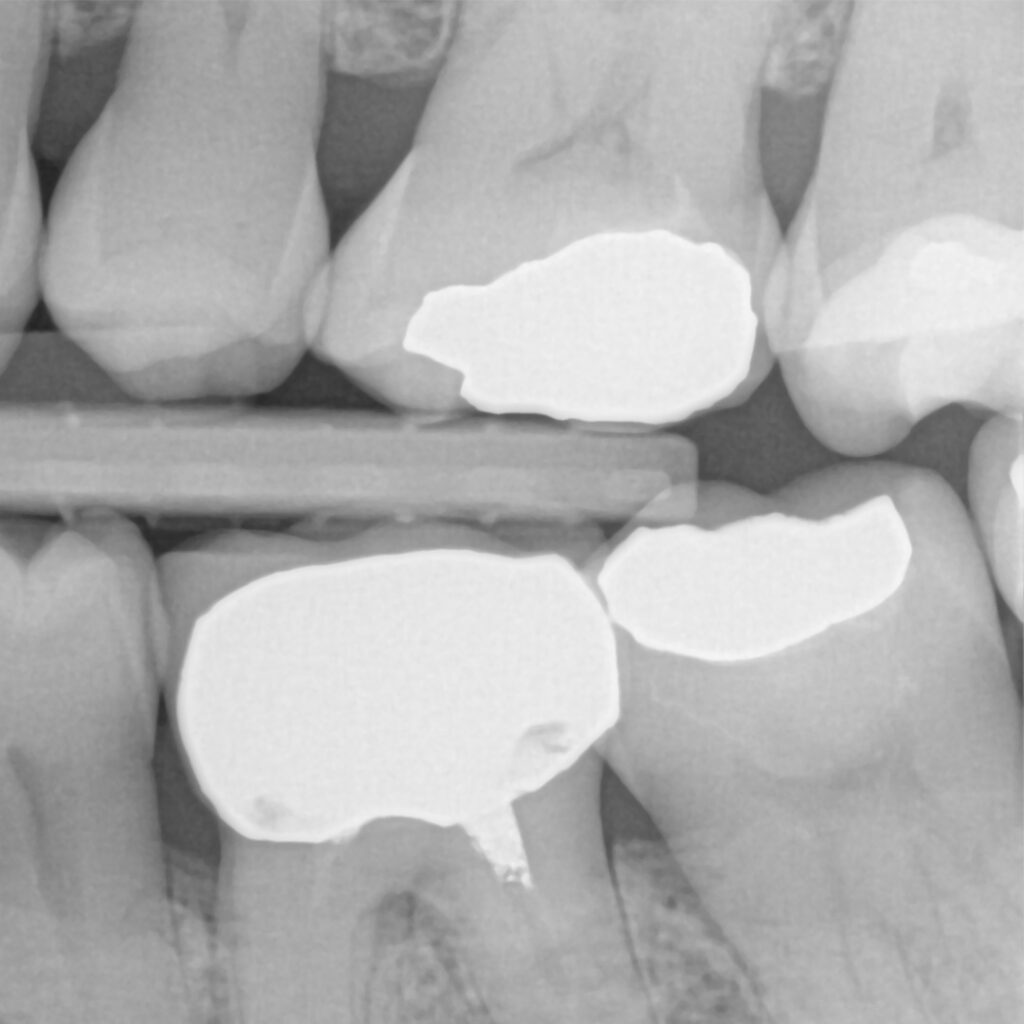

This clinical case involves a 54-year-old female patient who presented for her annual checkup. During the examination, secondary caries were detected on teeth #24 and #26.

Tooth #26 exhibited a large amalgam restoration, while tooth #24 had significant fractures, particularly in the mesial and distal regions. After evaluating the conditions of both teeth, it was decided to remove the amalgam in tooth #26 and composite fillings in tooth #24 due to the presence of secondary decay. For both teeth, the Predicta Bulk composite material, shade A2/B2 was chosen for restoration.